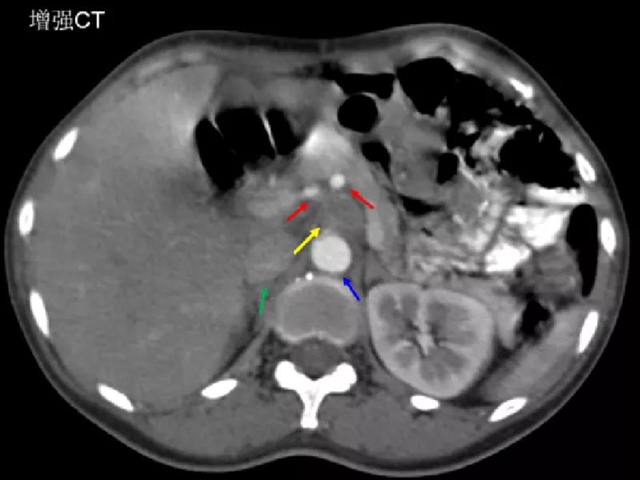

治疗前影像学评估肿瘤情况

(黄色箭头为转移淋巴结,红色箭头为肿瘤前方小动脉,绿色箭头为下腔静脉,蓝色箭头为腹主动脉)